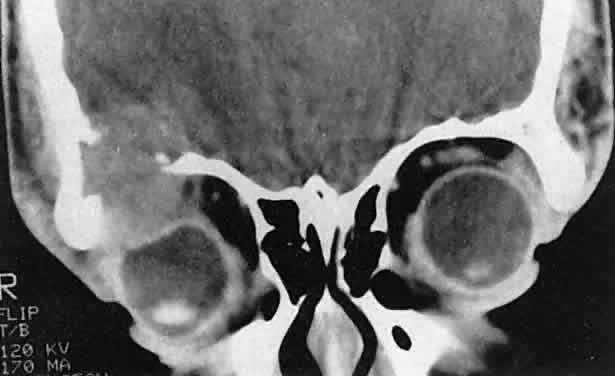

also should be submitted.  Fig. 3. A large metastatic focus of neuroblastoma has destroyed the body of the

sphenoid bone and has extended into both orbital apices. A second site

involves the outer portion of the right sphenoid wing and extends into

the orbit and the middle cranial and temporal fossas. The tumor originated

in the right adrenal gland. Fig. 3. A large metastatic focus of neuroblastoma has destroyed the body of the

sphenoid bone and has extended into both orbital apices. A second site

involves the outer portion of the right sphenoid wing and extends into

the orbit and the middle cranial and temporal fossas. The tumor originated

in the right adrenal gland.